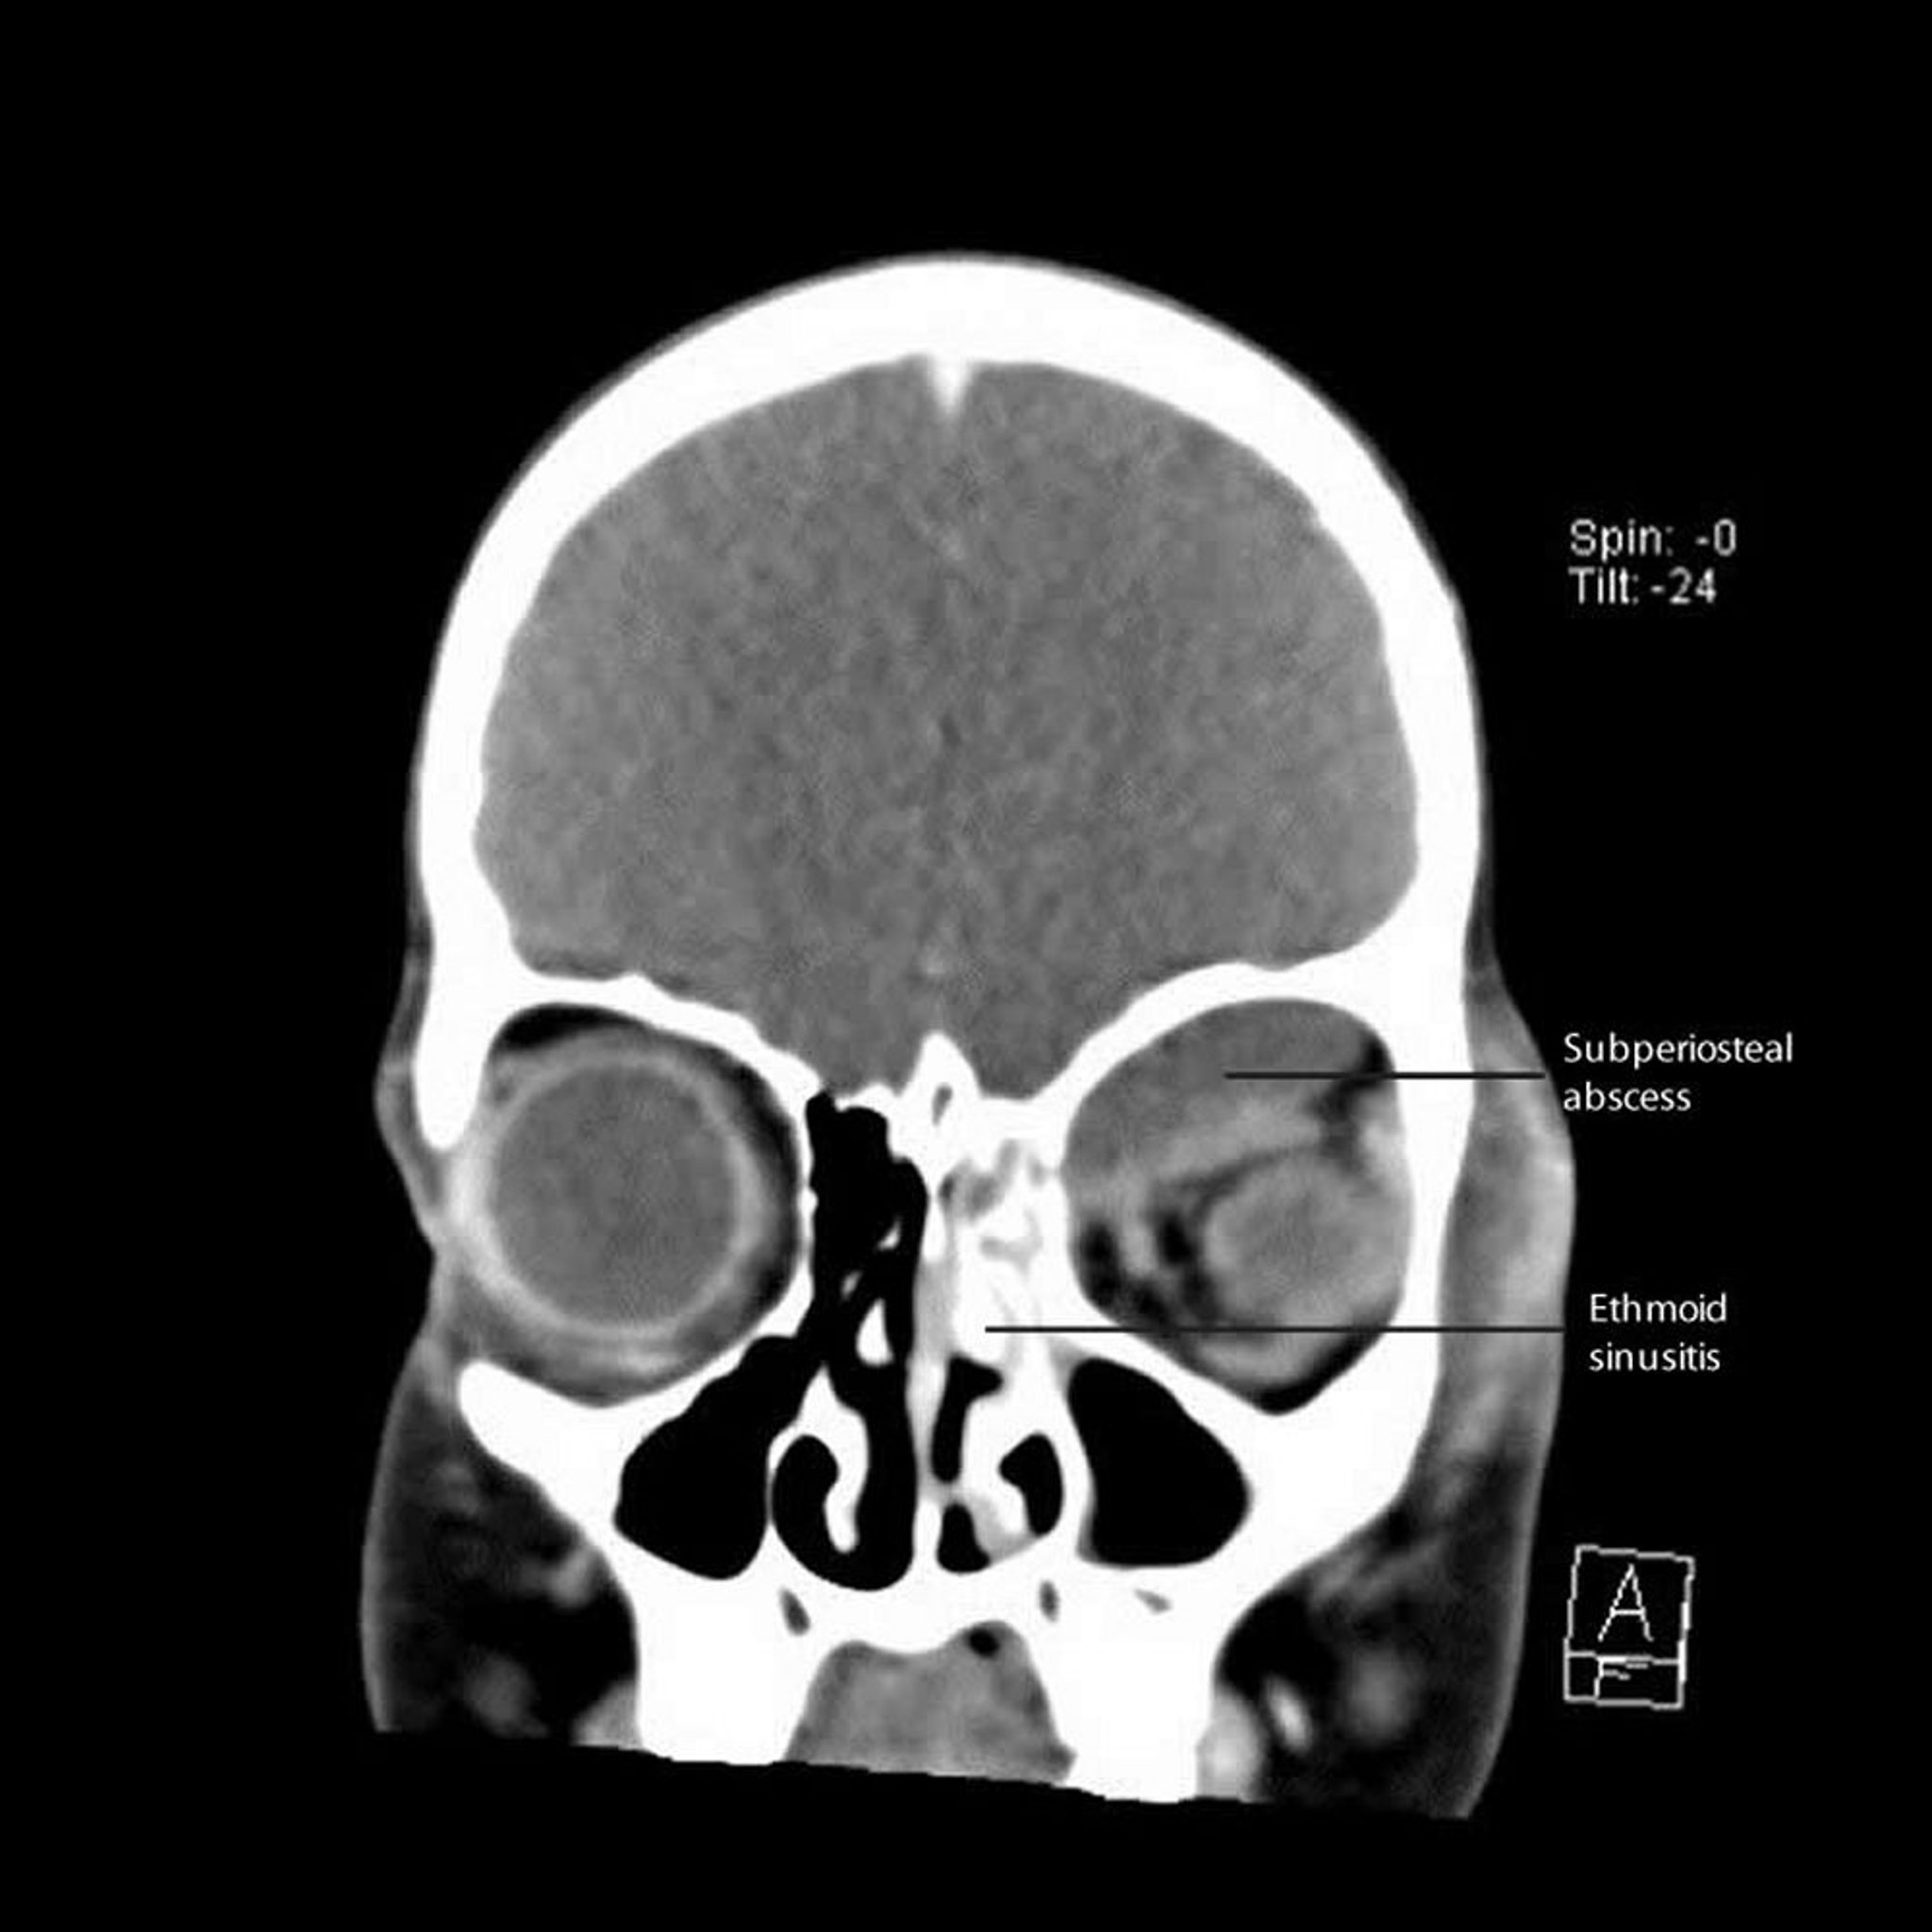

Orbital cellulitis is most often caused by extension of infection from adjacent sinuses, especially the ethmoid sinus. Less commonly, orbital cellulitis is caused by direct infection accompanying local trauma (eg, insect or animal bite, penetrating eyelid injuries), contiguous spread of infection from the face or teeth, or by hematogenous spread.

Because orbital cellulitis originates from large adjacent foci of fulminant infection (eg, sinusitis) separated by only a thin bone barrier, orbital infection can be extensive and severe. Subperiosteal fluid collections, some quite large, can accumulate; they are called subperiosteal abscesses, but many are sterile initially.

Subperiosteal abscesses, if large enough, can contribute to symptoms of orbital cellulitis such as swelling and redness of the eyelid, decreased ocular motility, proptosis, and decreased visual acuity.

The direction of proptosis may be a clue to the site of infection; eg, extension from the frontal sinus pushes the globe down and out, and extension from the ethmoid sinus pushes the globe laterally and out.